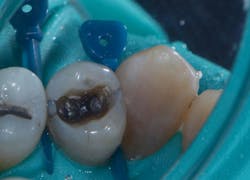

A 68-year-old patient presented with the upper right first premolar with occlusal amalgam and two distal marginal ridge fractures and discoloration under the mesial marginal ridge (figure 1). He previously had an extraction due to a fracture on his lower arch and wanted to treat the upper first premolar proactively. The existing occlusal amalgam was removed under rubber dam isolation. Caries were visualized clinically, and cracks were visualized with transillumination under both marginal ridges (figure 2). The premolar was prepared using a nonretentive cavity preparation design to allow the resin to flow in, out, and around the tooth (figure 3). Particle abrasion with 27 microns at 40 psi (PrepStart, Danville Products) was completed for microretention and biofilm removal before matrices, phosphoric acid etch (figure 4), and adhesive were placed.